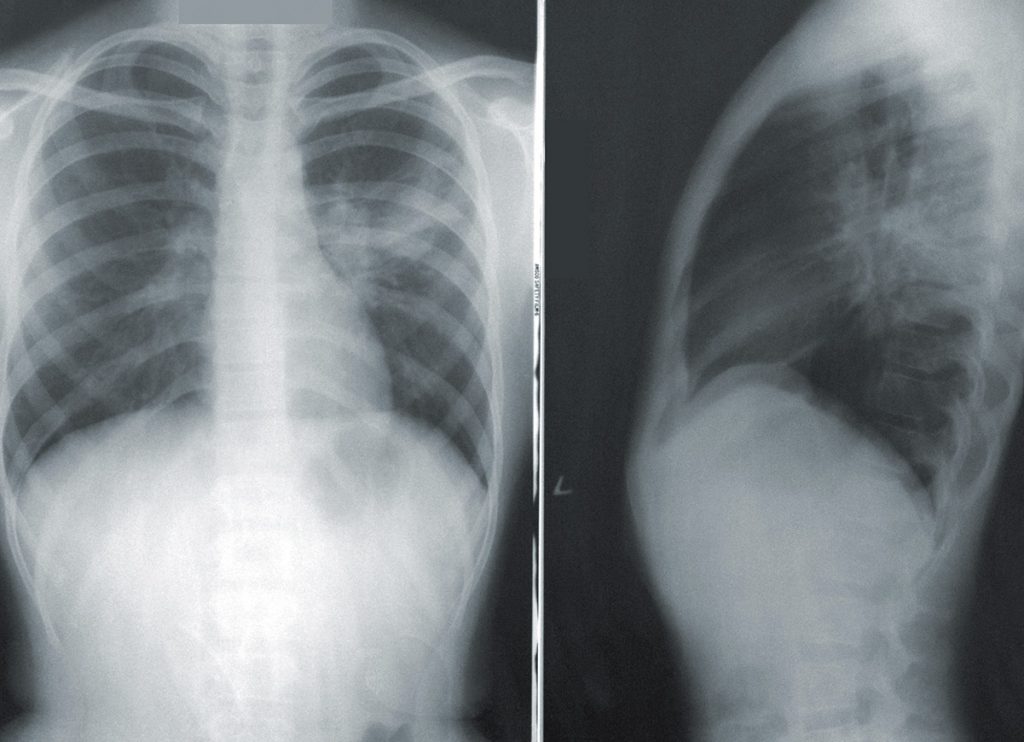

A las dos semanas volví. Lo encontré todavía más contento que la vez anterior (me daba la sensación de que era uno de sus pocos pacientes, y se alegraba de verme). Yo venía un poco atrasado, así que le pedí disculpas, pero me dijo que era mejor así, porque había tenido tiempo de consultar mi caso con otro médico, un especialista (¿no se suponía que él era el especialista?). Me mostró las radiografías en el computador, con toda clase de explicaciones. Ese tipo de médicos que te explica muchas cosas que uno no entiende, al menos yo. ¿Te fijas que aquí hay una pequeña deformación? ¿Ves esta inflamación aquí? Yo sólo veía manchas, como un test de Rorschach.

Después me dijo, con tono de que venía lo más importante: Fíjate aquí, ¿ves esta manchita? ¿De qué color es? Gris, le dije. ¡Exacto! respondió, con gran entusiasmo. ¿Y esta otra aquí al lado? Me empecé a poner un poco nervioso. Es decir, era una radiografía, un conjunto de manchas más o menos todas iguales.

¿Gris también? le consulté.

Esta respuesta lo molestó ostensiblemente.

“¿Pero son del mismo color, o color distinto?” volvió a preguntar

“Mismo color”

“Míralas bien (cada vez más alterado). Esta, y esta otra. ¿Son del mismo color?

Obviamente, me di cuenta que la respuesta correcta era que no, que no eran del mismo color. Pero entre que me molestaba un poco su pedagogía, y además objetivamente se veían exactamente del mismo color, decidí insistir en mi punto, aparentando total ingenuidad.

“Claro, del mismo color, ambas son grises”

Bueno, historia corta, se fue alterando cada vez más. Sacó una hoja de papel, las puso alternativamente al lado de ambas manchitas, me pidió que, con ayuda del contraste, me fijara bien, que si no notaba ninguna diferencia. Terminé por reconocer que una era un poco más oscura.

Esto lo tranquilizó por fin, y procedió explicarme que eso significaba que una estaba un poco inflamada, y no sé qué cosas más. Me dijo que necesitaba kine, y una plantilla, en un solo pie, para emparejar el largo de mis piernas. Me explicó con muchos detalles el tipo de plantilla que necesitaba (recta), como tenía que usarla, dónde comprarla. Cuando le pregunté si eran muy caras, se molestó también. Me dijo que él no sabía de esas cosas, como si lo hubiera importunado con una minucia. Después, me recomendó que pidiera una plantilla italiana, porque eran más blandas. De pronto, sacó una, y me hizo tocarla.